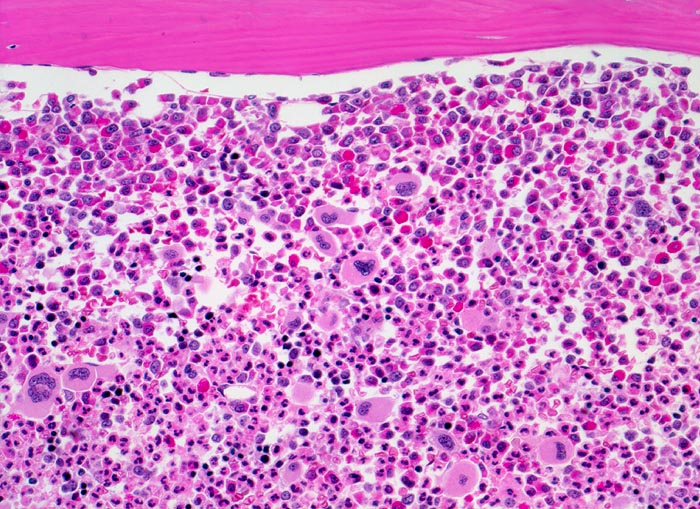

In der chronischen Phase zeigt das Knochenmark eine Hyperzellularität, welche auf eine Vermehrung der neutrophilen Granulozyten und deren Vorläufer zurückzuführen ist. Der paratrabekuläre Streifen unreifer Granulozyten kann verbreitert sein von normal 2-3 Zellschichten auf 5-10 Zellschichten. Blasten machen weniger als 5% der Knochenmarkzellen aus. Eine Blastenzahl von mehr als 10% deutet auf eine Transformation in ein akzeleriertes Stadium und von mehr als 20% entspricht einer Blastenkrise mit Transformation in eine akute Leukämie. Die Megakaryozyten sind typischerweise kleiner als normal, haben hypolobierte Kerne und sind bei 40-50% der Patienten vermehrt. Der Prozentanteil der erythroiden Vorstufen ist gewöhnlich vermindert (G:E Ratio >5:1. Die initiale Knochenmarkbiopsie zeigt bei 40% der Patienten eine Vermehrung von Reticulinfasern assoziiert mit einer erhöhten Anzahl Megakaryozyten. Das Ziel der histologischen Untersuchung des Knochenmarks besteht darin, den Anteil an Blasten im Knochenmark und damit das Stadium der Erkrankung festzulegen. Bis zu einem Blastengehalt von weniger als 10% der kernhaltigen Zellen spricht man von einer chronischen Phase, zwischen 10 und 20% von einer akzelerierten Phase und bei über 20% liegt eine akute Leukämie vor.

• Fast 100% Zellularität des blutbildenden Marks (praktisch keine Fettzellen, sogenanntes "packed marrow").

• Stark vermehrte, ausreifende Myelopoese.

• Der paratrabekuläre Saum unreifer myeloischer Zellen ist verdickt auf 5 bis 6 Zellen.

• Verdrängung der Erythropoese.

• In Gruppen liegende vermehrte nacktkernige (= kein Zytoplasma) verkleinerte Mikromegakaryozyten mit hypolobierten Kernen.